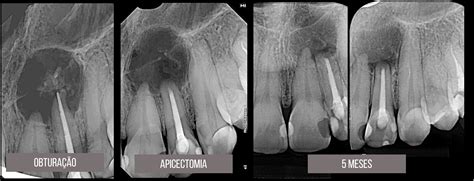

Son varias las técnicas odontológicas utilizadas para salvar las piezas dentales y cuidar de nuestro estado bucodental. La apicectomía es un proceso de cirugía maxilar que permite amputar el ápice, que es la porción más distal de la raíz de una pieza dental dañada y de los tejidos anexos debido a la persistencia de una infección que no se puede resolver de otra manera.

Suele recurrirse a este tratamiento cuando las técnicas endodónticas fallan o no sea viable su aplicación. Se procede a despegar, elevando un colgajo, el tejido blando y la encía, para dejar expuesto el ápice tras ampliar el defecto óseo causado por la infección en el hueso que da soporte a la pieza dental. Una vez realizada esta fase del tratamiento, se prepara la cavidad del conducto para rellenarla con un sellador especial, concretamente, con una sustancia llamada material trióxido agregado (MTA). Luego, se sutura la encía sobre la zona que se ha hecho la incisión.

La apicectomía se debe realizar cuando la infección dental no se controla mediante otras técnicas conservadoras como la endodoncia. En ocasiones puede haber agudizaciones de la inflamación y producirse un absceso periapical agudo o una celulitis, procesos de mayor gravedad. No obstante, a veces no se puede salvar el diente y se debe recurrir a técnicas no conservacionistas.

La endodoncia es una técnica muy recurrida en las clínicas donde apostamos por las técnicas odontológicas conservadoras. La realizamos de forma asidua para corregir caries, fracturas y otros problemas que no tienen solución con intervenciones más simples. Más del 90% de las endodoncias tienen éxito. No obstante, hay algunos pocos casos que, aunque se realice de forma adecuada, el tratamiento del conducto no garantiza la eliminación de la infección y se debe recurrir a tratamientos como la apicectomía o, en caso de no ser viable, extraer la pieza.